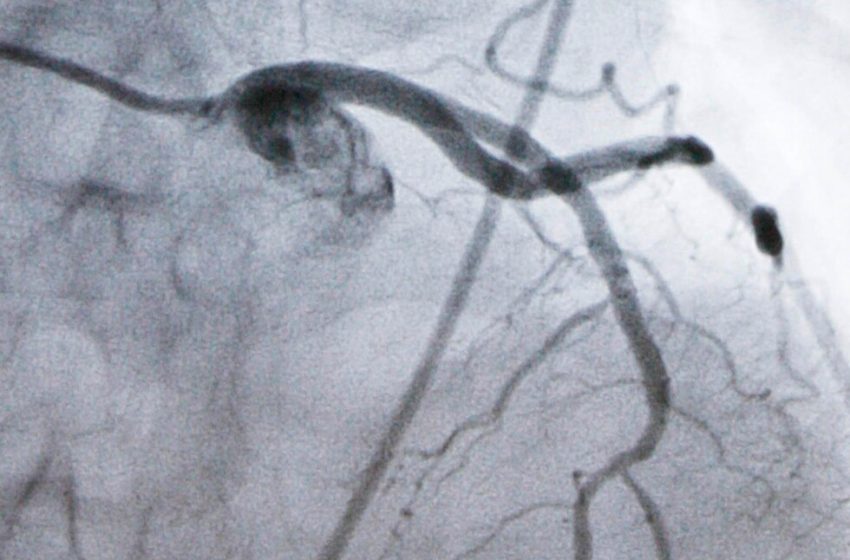

Heart disease is the nation’s leading cause of death and high LDL cholesterol, which causes plaque to build up in arteries, is a top risk factor for heart attacks and strokes. While an LDL level of 100 is considered fine for healthy people, doctors recommend lowering it to at least 70 once people develop high cholesterol or heart disease — and even lower for those at very high risk.